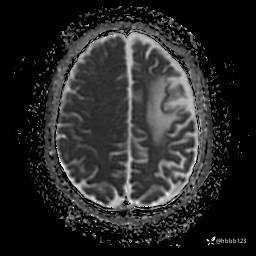

DWI: